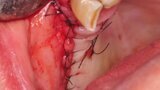

Osteonekroza występująca po zastosowaniu bisfosfonianów